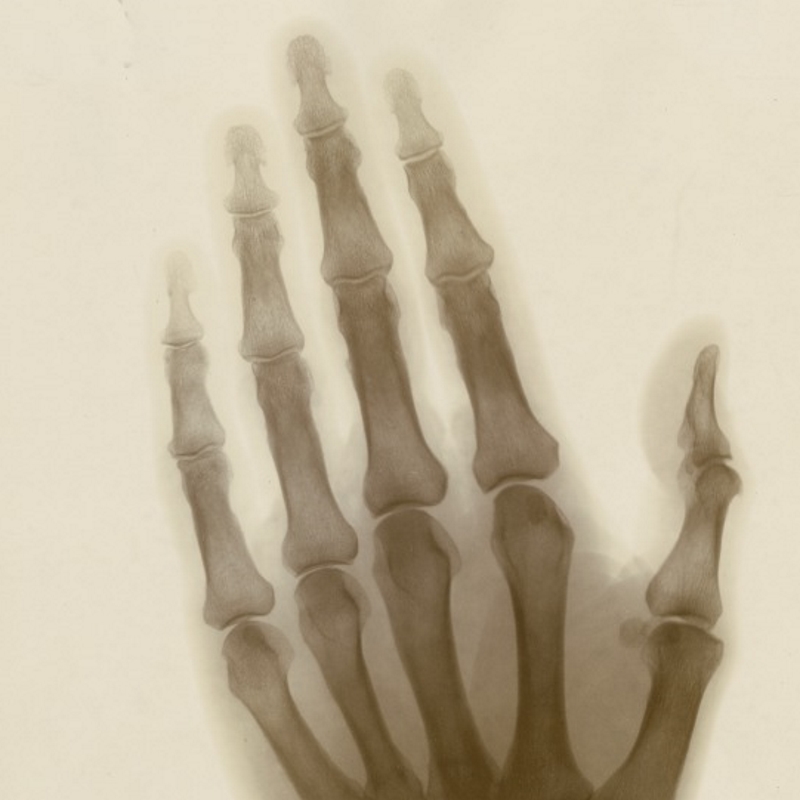

An avid photographer from childhood, Swinton produced countryside landscapes and portraits of friends and family, as well as attempting to capture electrical phenomena. His X-ray images of his own hand, plus those of Crookes, Armstrong and Kelvin, were exhibited at the Royal Society Conversazione on 6 May 1896 and are particularly fascinating, but they were not his only scientific trial.

Young Swinton experimenting with photography (ACS/6/2/2/3); X-ray photograph of Swinton’s own hand, 1896 (ACS/6/2/4/3); oscillatory discharge from positive to negative (ACS/6/1/6)